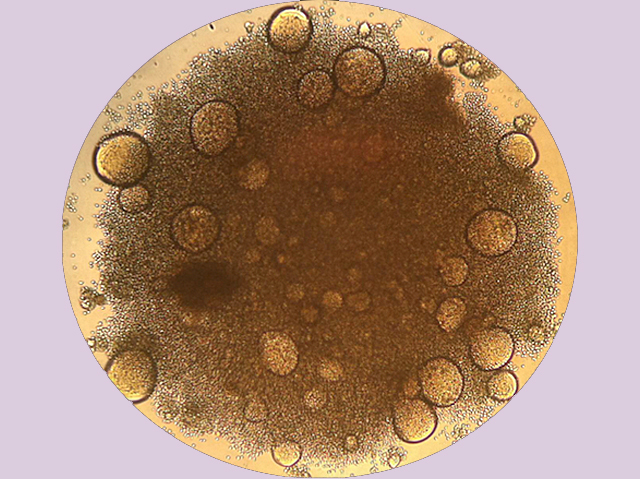

These strange blobs are clusters of immune T cells infected with human immunodeficiency virus (HIV) – the virus that causes AIDS. The infected cells fuse together, forming large structures known as syncitia. Scientists have discovered that one of the genes in HIV encodes a protein called Env, which encourages the fusion of infected cells. But although this cellular get-together certainly happens with cells grown in plastic dishes in the lab, it’s not clear whether it happens in infected patients. This idea was controversial for a long time, and although there was some evidence that certain types of HIV-infected cells could club together inside the body, T cells couldn’t. The latest research suggests that syncitia do form when T cells are infected with HIV inside a person. But rather than being round blobs like these, they take on a more elongated, spidery shape, which helps to spread the infection to nearby tissues.